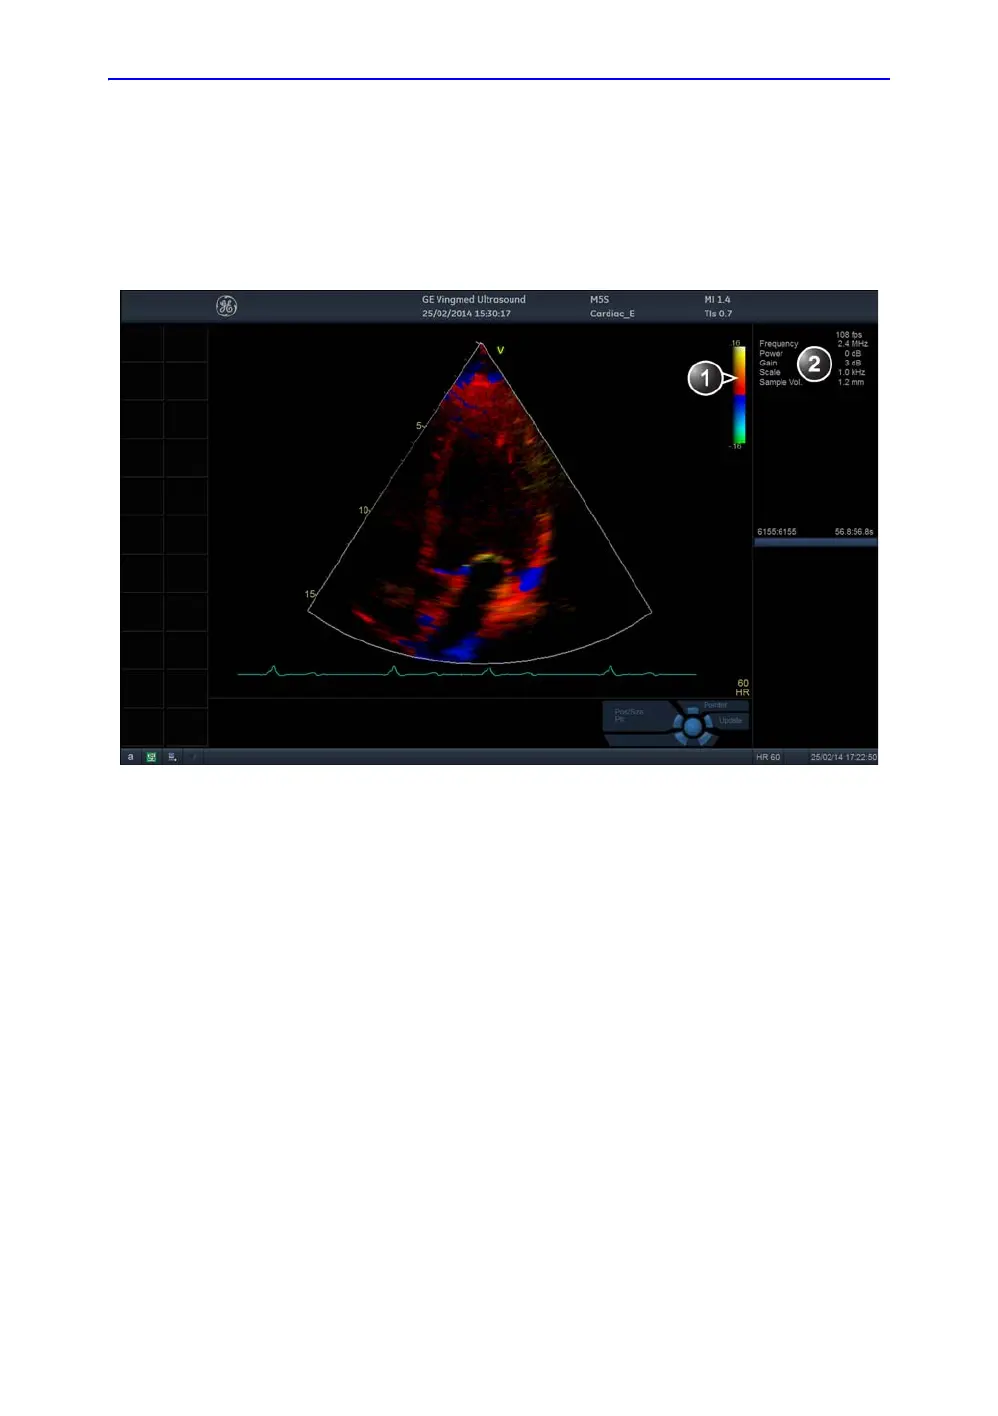

TVI overview

Figure 4-15. The TVI Mode screen

1. TVI color bar

2. Parameter window